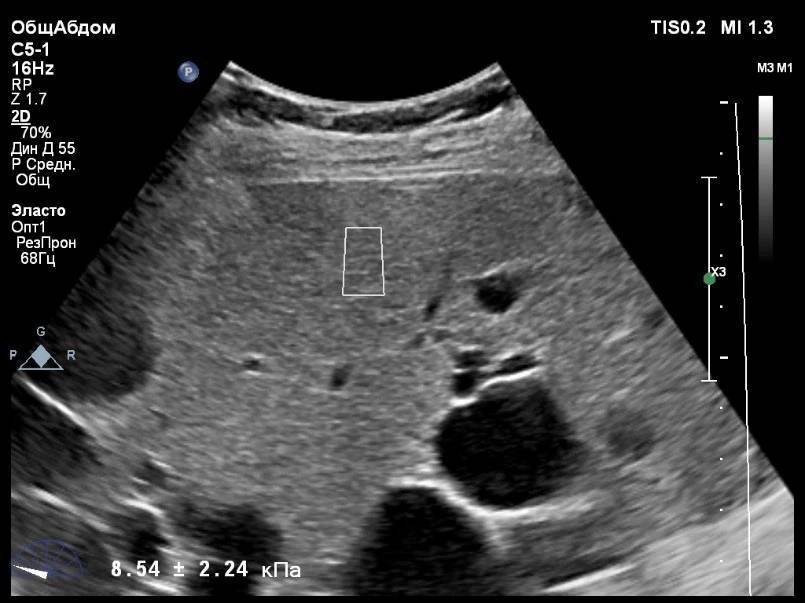

В первую очередь, это комфортное безболезненное обследование. Но основное преимущество эластографии заключается в самой большой информативности по сравнению с другими видами диагностики. Не так давно единственной возможностью выявить фиброз выступала биопсия. Она является оперативным вмешательством и не применима для некоторых пациентов. К тому же, гистологический анализ проводился на материале, взятом из одного участка печени, что снижало достоверность диагноза. К преимуществам эластометрии следует отнести: